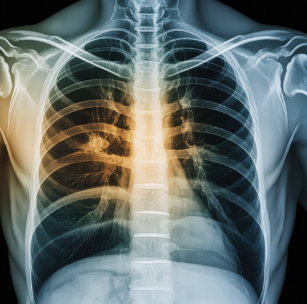

6. 기침 후 가슴 통증

기관지 염증이 심해지면 흉통이 생기거나 호흡이 답답할 수 있습니다.